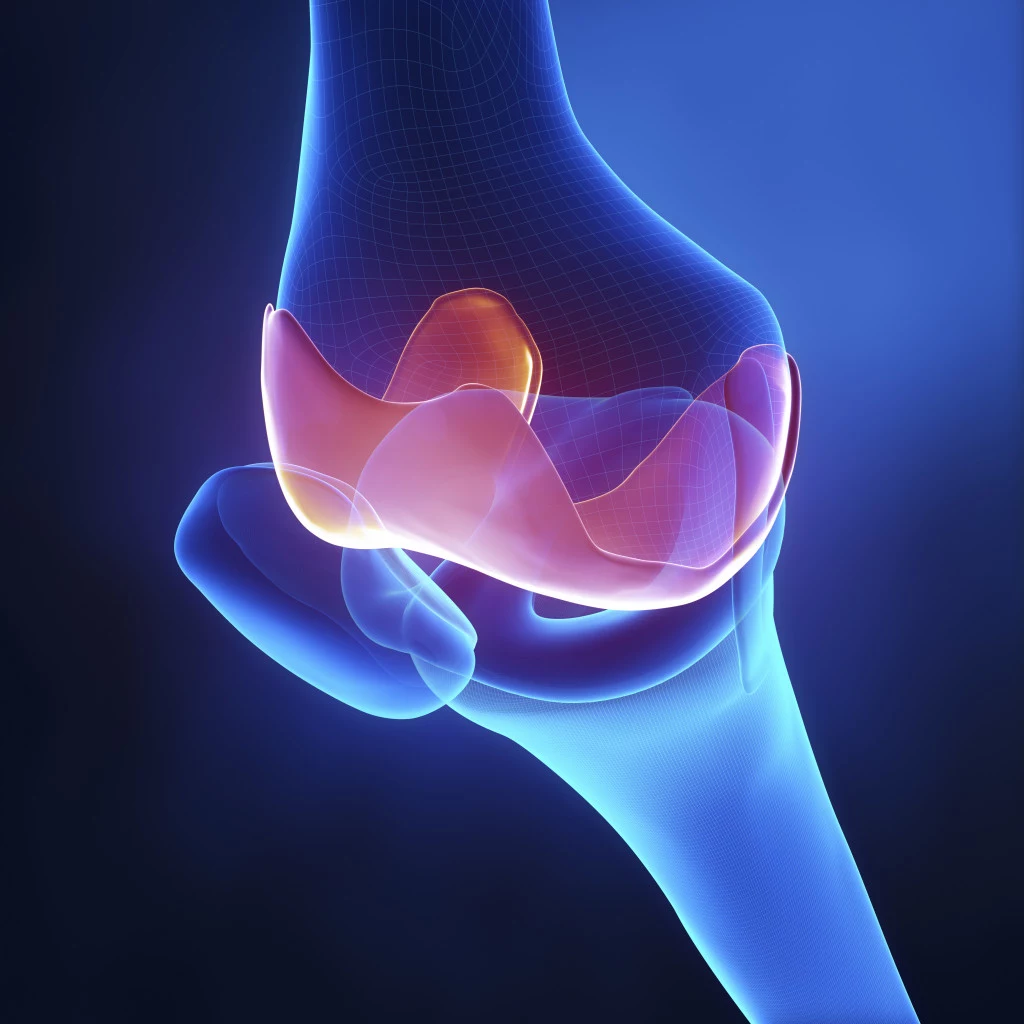

Uszkodzenia łąkotek

Łąkotka to chrząstka, która spełnia rolę "poduszki" dla naszych kolan. Urazy i zmiany zwyrodnieniowe mogą powodować jej ścieranie się. W takim wypadku czujemy podrażnienie i ból oraz pojawia się opuchlizna na zewnątrz kolana lub wewnątrz, w zależności od tego, która łąkotka została uszkodzona.